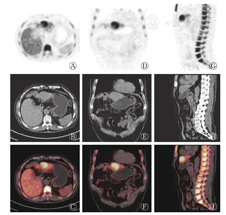

本研究获得我院伦理委员会批准(批准号:201708093),患者于检查前签署了知情同意书。18F-FDG PET/CT采用德国西门子Biograph mct-64,患者空腹6h以上,空腹血糖水平低于10 mmol/L,静脉注射18F-FDG 4.0×109 Bq/kg,安静状态下休息60 min后行18F-FDG PET/CT显像(图2)。图像显示:肝左外叶上段结节,18F-FDG代谢稍增高,SUVmax为2.8,病灶与邻近肝实质分界模糊,难以确定病灶性质。次日行18F-氟代脱氧胸腺嘧啶(18F-fluoro-3′-deoxy-3′-L- fluorothymidine,18F-FLT)显像(图3),图像提示:肝左叶病灶代谢活跃,SUVmax为11.2,病灶与邻近正常肝实质代谢差异明显,高度怀疑肝癌。

18F-FLT PET/CT imaging of the liver (male,69 years old )

18F-FLT是近年来比较受关注的新型正电子示踪剂,属于胸腺嘧啶的类似物,在限速酶胸苷激酶(thymidine kinase1 ,TK1)的作用下参与DNA合成,其利用TK1催化的磷酸化作用来评价DNA的复制过程,通过反映TK1的活性间接反映肿瘤细胞的增殖状况,从而评估肿瘤细胞DNA的合成和细胞增殖活性,有助于对肿瘤进行良恶性鉴别、疗效评估和预后判断,是目前性能较好的核酸代谢显像剂[7,8,9]。在正常生理情况下,18F-FLT在肝脏的代谢比较旺盛,但它仍然可以反映肝癌细胞的增殖状态。本文中该病例在行18F-FLT PET/CT显像时,病灶区域的代谢明显高于肝实质,提示病灶增殖活跃,怀疑肝癌。在PET/CT图像中不难看出:两种显像剂对同一病灶的显像差异明显,18F-FLT可以比18F-FDG更好地反映肿瘤细胞的增殖状态。18F-FDG和18F-FLT的联合使用及18F-FLT的重要补充价值对该病灶的早期判断及临床医师的决策起了重要作用。